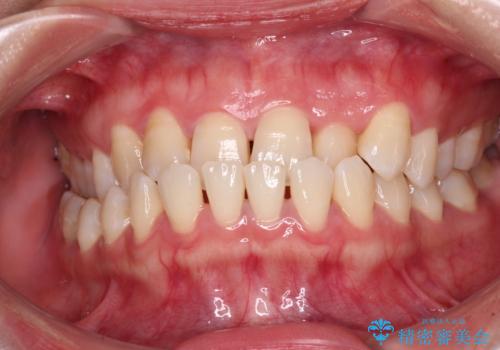

前歯のクロスバイトを短期間で解消 目立たないワイヤー矯正

前歯が反対に咬んでいる インビザラインによる矯正治療